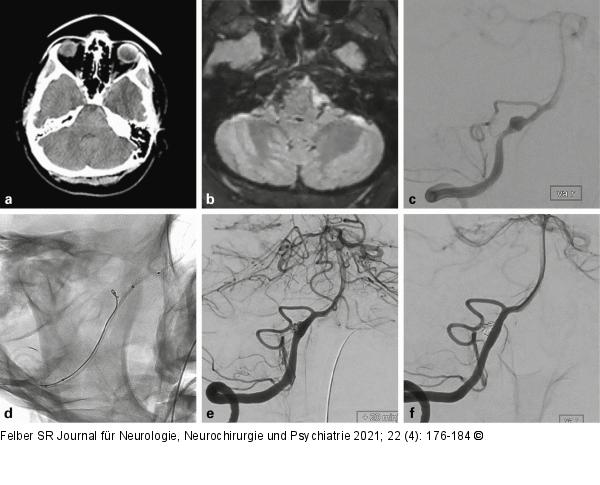

Abbildung 2a-f: Dissektionsaneurysma

Die 45-jährige Patientin hatte über einige Tage Nackenschmerzen, dann Vernichtungskopfschmerz. Im CT (a) zeigte sich eine präpontine Blutansammlung. Im MRT (b) waren ältere und frischere Blutabbauprodukte nachweisbar. Die Angiographie (c) bestätigte ein fusiformes Aneurysma des rechten proximalen intraduralen V4-Segmentes mit vorgeschalteter Stenose. Ein Mikrokatheter wurde durch das Aneurysma in das distale V4-Segment eingeführt und darüber ein flusskorrigierender Stent (p64 3,5 × 21 mm, Phenox, Bochum, Deutschland) vorgebracht. Ein zweiter Mikrokatheter wurde im Aneurysma positioniert und darüber eine Coil vorbereitet (d). Während der flusskorrigierende Stent freigesetzt wurde, erhielt die Patientin die gewichtsadaptierte Initialdosis Eptifibatid (Intergrilin®, Glaxo Smith Kline, München, Deutschland) über den Führungskatheter. Gleichzeitig wurden über den zweiten Mikrokatheter Coils in das Aneurysma eingebracht und dann 500 mg Aspirin (Aspirin i.v., Bayer AG, Leverkusen, Deutschland) intravenös gegeben (e). Die intravenöse Erhaltungsdosis Eptifibatid wurde für 24h weitergeführt. Im Anschluss wurde für 12 Monate eine duale Thrombozytenaggregationshemmung mit ASS 100 mg/d und Clopidogrel 75 mg/d durchgeführt. Die Angiographiekontrolle nach einem Jahr (f) zeigte das behandelte V4-Segment mit normalem Kaliber, das Aneurysma war ausgeschaltet, es bestand kein neurologisches Defizit. |